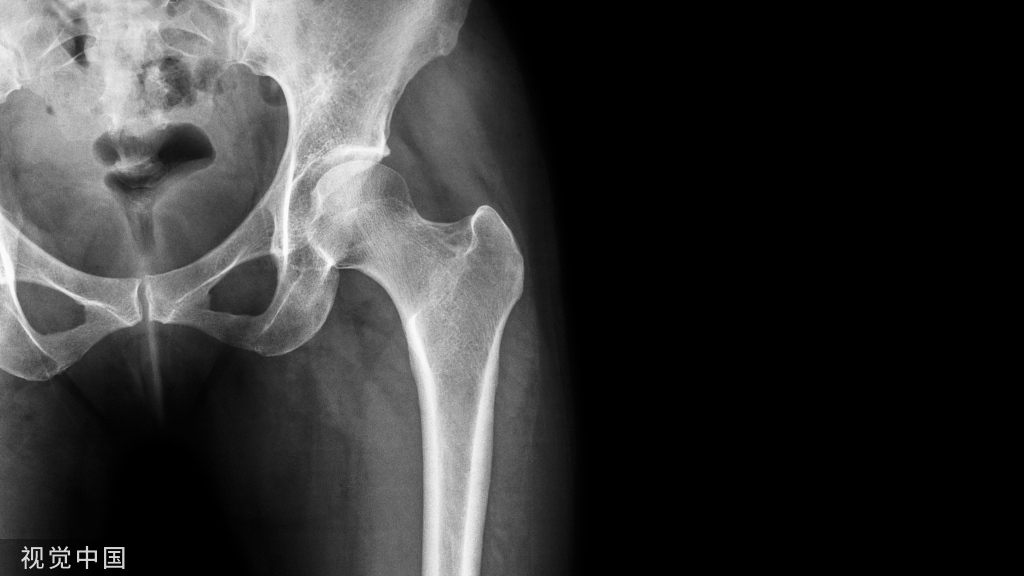

图注:55岁女性,腰椎翻修手术硬膜撕裂,术后第7天出现神经系统变化(神志错乱、失语等)。头颅CT示左侧额叶、顶叶、颞叶有硬膜下血肿,中线移位。患者被紧急送至手术室进行硬膜下血肿的清除。手术后失语症完全消失,头颅CT显示左侧血肿完全清除。